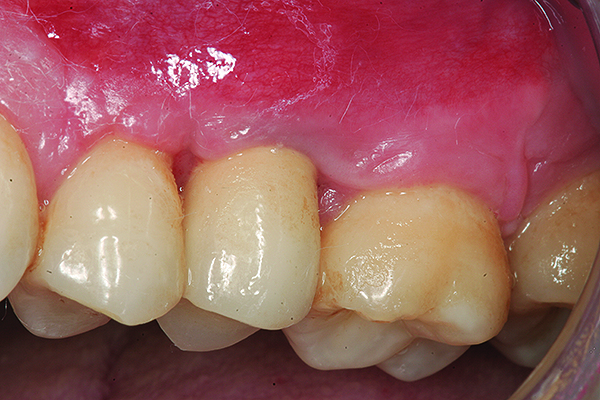

The implant restoration and surrounding soft tissue seen in Fig 3, 5 years following treatment.

Figure 4